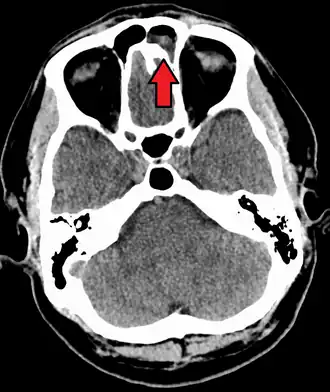

Intracranial complications

The proximity of the sinuses to the brain makes brain infections one of the most dangerous complications of acute bacterial sinusitis, especially when the frontal and sphenoid sinuses are involved. These infections can result from invasion of anaerobic bacteria through the bones or blood vessels. Abscesses, meningitis, and other life-threatening conditions may occur. In rare cases, mild personality changes, headache, altered consciousness, visual problems, seizures, coma, and even death may occur.[33]

Imaging by either X-ray, CT, or MRI is generally not recommended unless complications develop.[66] Pain caused by sinusitis is sometimes confused for pain caused by pulpitis (toothache) of the maxillary teeth, and vice versa. Classically, the increased pain when tilting the head forwards separates sinusitis from pulpitis.[68]

For sinusitis lasting more than 12 weeks, a CT scan is recommended.[66] On a CT scan, acute sinus secretions have a radiodensity of 10 to 25 Hounsfield units (HU). In a more chronic state, they become more viscous, with a radiodensity of 30 to 60 HU.[69]